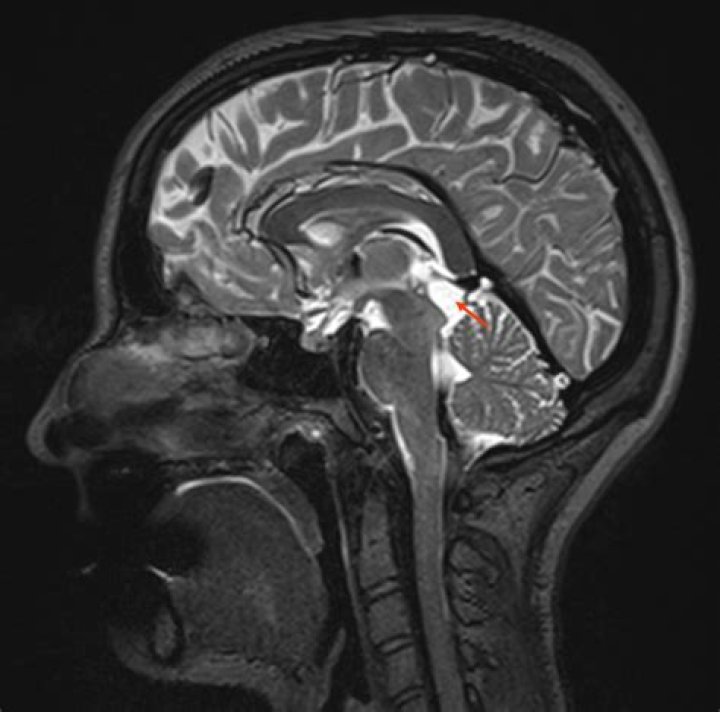

Where is a pineal cyst?

Pineal cysts are fluid-filled spaces within the pineal gland. The pineal gland sits nearly in the center of your brain, and is responsible for hormones related to sleep-wake cycle. Pineal cysts are common, occurring in about 1-5% of the population. These cysts are benign, which means not malignant or cancerous.